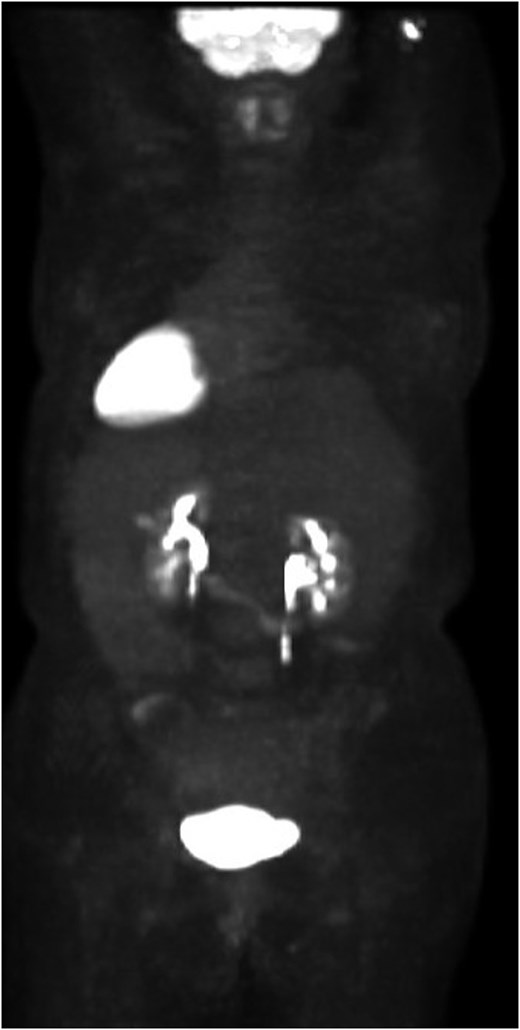

She completed six cycles of adjuvant leucovorin/folinic acid, 5-fluorouracil, and oxaliplatin (FOLFOX) before developing pelvic and perineal discomfort. CT imaging demonstrated suspicious masses of the right abdominal wall (Fig. 1A), right ovary (Fig. 1B), anterior rectum (Fig. 1C), and left inguinal lymph node (Fig. 1D). A fine needle aspiration of the peritoneum and cervix confirmed metastatic colorectal adenocarcinoma. Given the progression despite being on chemotherapy, a multidisciplinary discussion was made to initiate pembrolizumab. The patient completed 1 year of therapy (20 cycles), which she tolerated well. Restaging with esophagogastroduodenoscopy (EGD), colonoscopy, and positron emission tomography (PET) demonstrated stable disease without progression (Fig. 2). MRI imaging redemonstrated essentially stable appearing right rectus abdominus muscle mass measuring 2.1 × 1.6 × 2.2 cm (Fig. 3A), two suspicious ovarian lesions measuring 2.9 × 1.7 × 3.2 and 2.0 × 1.2 × 1.9 cm (Fig. 3B), an additional mass abutting the anterior peritoneal reflection measuring 3.7 × 2.9 × 3.1 cm (Fig. 3C), and prominent 12 mm left inguinal lymph node (Fig. 3D).

Patient’s preoperative PET scan, which demonstrates no significant hypermetabolic parenchymal lesions, lymph nodes, or masses.